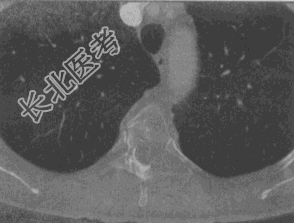

- 单项选择题女,58岁, 背部隐痛2个月余,1年前行乳癌根治术, 结合影像学检查,最可能的诊断

E、脊柱转移瘤